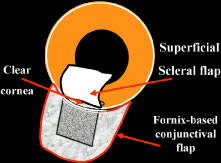

to be well tolerated. The small fornix-based flap can be closed by stretching it toward one side, especially

if a radial relaxing incision approximately 2 mm long

and extending from the limbus has been performed (Fig. 11). This closure can be done with the same suture used to close the corneoscleral

incision, or it can be coapted with the wet-field cautery.   Fig. 11. Fornix-based flap procedure. A. With a scissors or knife, the conjunctiva is incised as close to the limbus

as possible. B. The incision is widened. The surgeon uses forceps to stretch the tissue. The

scissors cut inferiorly so that no remnant of conjunctiva is left

on the globe. C. Tissue is separated from the globe by inserting the scissors with the

tips closed and then spreading them bluntly. D. Blunt dissection is continued until the sclera is cleaned adequately. Bleeding

from the cut conjunctival vessels is almost inevitable and usually

exceeds the bleeding that occurs when a limbus-based flap is raised. E. A radial cut at the edge of the peritomy will improve visualization of

the sclera and permit a neat closure of the conjunctiva. F. The cut edge of a fornix-based flap is pulled inferiorly and secured with

a 10-0 nylon purse-string suture. G. With large incisions, it usually is necessary to suture both edges to

ensure tight closure. (Spaeth GL. Glaucoma surgery. In Spaeth GL (ed). Ophthalmic Surgery: Principles

and Practice. Philadelphia: WB Saunders, 1990.) Fig. 11. Fornix-based flap procedure. A. With a scissors or knife, the conjunctiva is incised as close to the limbus

as possible. B. The incision is widened. The surgeon uses forceps to stretch the tissue. The

scissors cut inferiorly so that no remnant of conjunctiva is left

on the globe. C. Tissue is separated from the globe by inserting the scissors with the

tips closed and then spreading them bluntly. D. Blunt dissection is continued until the sclera is cleaned adequately. Bleeding

from the cut conjunctival vessels is almost inevitable and usually

exceeds the bleeding that occurs when a limbus-based flap is raised. E. A radial cut at the edge of the peritomy will improve visualization of

the sclera and permit a neat closure of the conjunctiva. F. The cut edge of a fornix-based flap is pulled inferiorly and secured with

a 10-0 nylon purse-string suture. G. With large incisions, it usually is necessary to suture both edges to

ensure tight closure. (Spaeth GL. Glaucoma surgery. In Spaeth GL (ed). Ophthalmic Surgery: Principles

and Practice. Philadelphia: WB Saunders, 1990.)